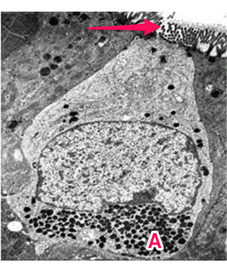

Enteroendocrine cell (Open type) A: Basal electron dense granules

Enteroendocrine cell (Closed type) A: basal electron dense granules